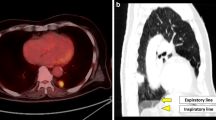

Fluorodeoxyglucose (FDG)-PET has been a useful tool for the evaluation of treatment response after conventional fractionated radiation therapy for NSCLC. It is unclear whether FDG-PET is equally useful in patients who received SABR for lung tumors. Data in the literature on the use of FDG-PET in the evaluation of post-SABR response are emerging [3]. One of the earliest studies includes a retrospective study from Indiana University, where 14% of patients treated with SABR for medically inoperable NSCLC in a prospective trial maintained a moderate standardized uptake value (SUV) (defined as higher than 2.5) 22–26 months after treatment and upon longer follow-up (42–49 months), remaining alive without evidence of disease recurrence [16]. In an Indiana University pilot trial of serial FDG-PET in patients with medically inoperable stage I non-small cell lung cancer treated with SABR, serial FDG-PET/CT was done before SBRT and at 2, 26, and 52 weeks after SABR. It was observed that patients with low pre-SBRT SUV were more likely to have an initial 2-week rise in SUV, and patients with high pre-SABR SUV frequently had a decline in SUV 2 weeks after treatment [17]. Six out of 13 patients had primary tumor maximum SUV of >3.5 at 12 months after SBRT but did without any evidence of local disease failure on subsequent follow-up. In a study from Kyoto University, Matsuo demonstrated that FDG uptake tended to be intense and well defined at early periods after SABR, especially within 6 months, and was faint and ill-defined at later periods. Moderate to intense FDG uptake on PET soon after SABR did not always represent a residual tumor [18]. Figures 3 and 4 showed the serial changes on FDG-PET after SABR.

A 75-year-old gentleman with recurrent medically inoperable stage I NSCLC (pre-treatment SUV of 4.2) was treated with SABR to a dose of 45 Gy in 5 fractions. There was an increase of SUV after 7 months. The SUV then decreased to 4.7 at 10 months. Subsequent follow-up with CT did not show evidence of progression of fibrotic changes, and he had no evidence of disease 2.5 years after SABR

The right lung nodule was biopsy proven to be metastatic cervical carcinoma. Fused data from the PET/CT are shown (a). The lesion was treated with 12 Gy × 5 fractions and was reimaged at 4 months (b) and 13 months (c). Note the inflammation that was induced at 4 months and resolved at 13 months with lung parenchymal changes. Presumably, this showed evolution and resolution of acute radiation changes. The patient did not develop symptoms of radiation pneumonitis